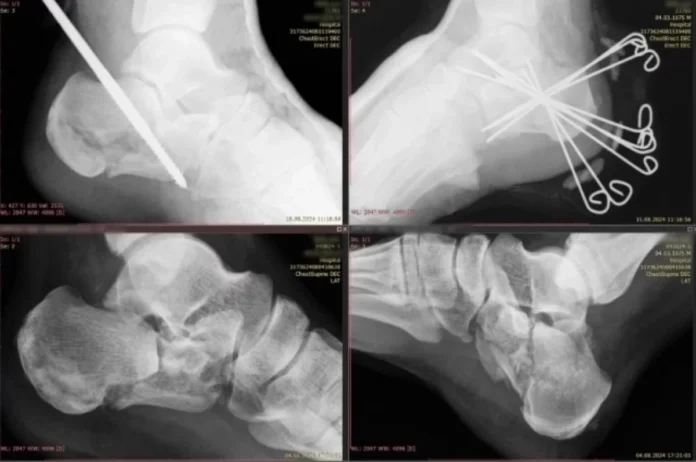

В результате несчастного случая — падения с высоты трех метров — мужчина получил перелом обеих пяточных костей, что полностью лишило его возможности передвигаться самостоятельно. Благодаря мастерству хирургов была выполнена виртуозная операция, а затем специально сформированная мультидисциплинарная бригада медицинских специалистов провела комплексный курс реабилитации.